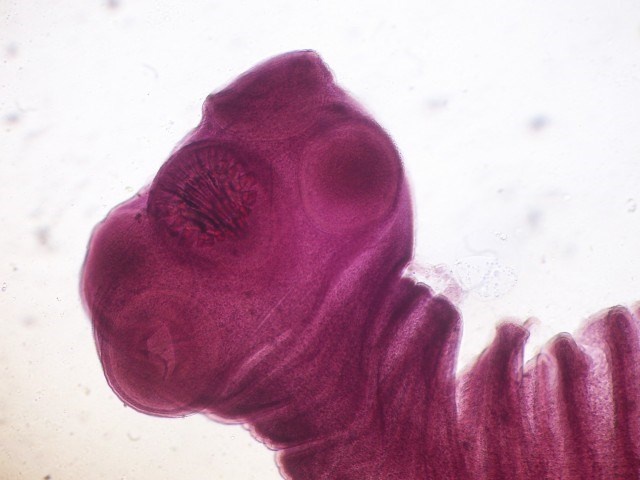

Nhiễm ấu trùng sán lợn có tên là Taenia solium, thường lây truyền từ người sang người thông qua thực phẩm chưa nấu chín. Trứng của nó thường tạo ra các u nang trong mô người, bao gồm cả trên não và mắt. Khi bị ấu trùng này tấn công, mắt sẽ bị mờ, bong võng mạc. |

![]() |